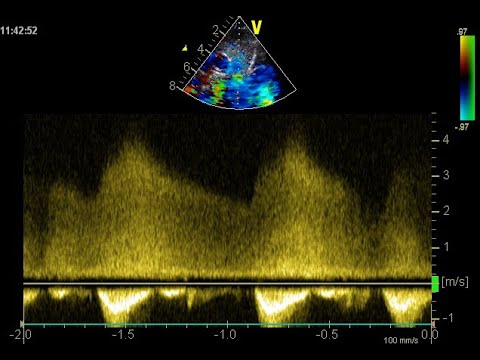

Les oreillettes et les auricules sont en amont de ce qui peut paraitre important ; l’amont de tout mais rien d’important en cardiologie. Pour nous, cardiologues congénitalistes, ce sont des structures respectées et pas seulement des lieux de passage. Si les communications interatriales sont le plus souvent simples, il est en de difficiles et les questions autour de l’anatomie des oreillettes restent pertinentes tout comme celles qui justifient que nous intervenions pour d’autres raisons que les honoraires de l’implantation d’une prothèse.